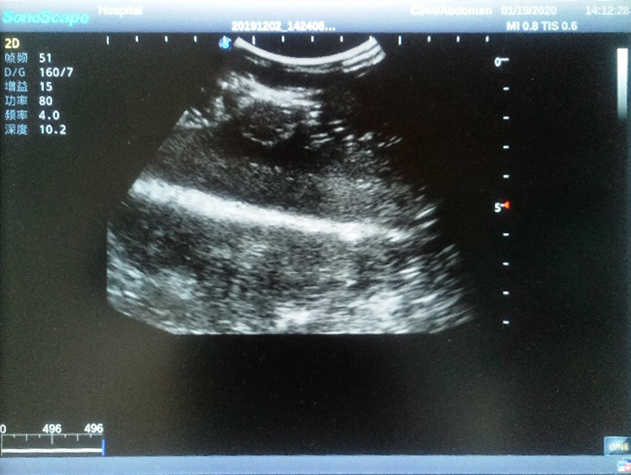

Outline

The Breast Ultrasound Examination Model allows users to develop and practice the skills necessary to gain proficiency in breast palpation, using ultrasound for normal and abnormal imaging and biopsy. It simulates adult female breasts with realistic size and appearance.

2)  Each model contains 8 space-occupying lesions of varying sizes, different in touch, elasticity and ultrasonogram

4) Biomimetic material allowing users to see clear and real normal tissues and space-occupying lesions that are hyperechoic, hypoechoic and isoechoic as they would see in the clinical environment